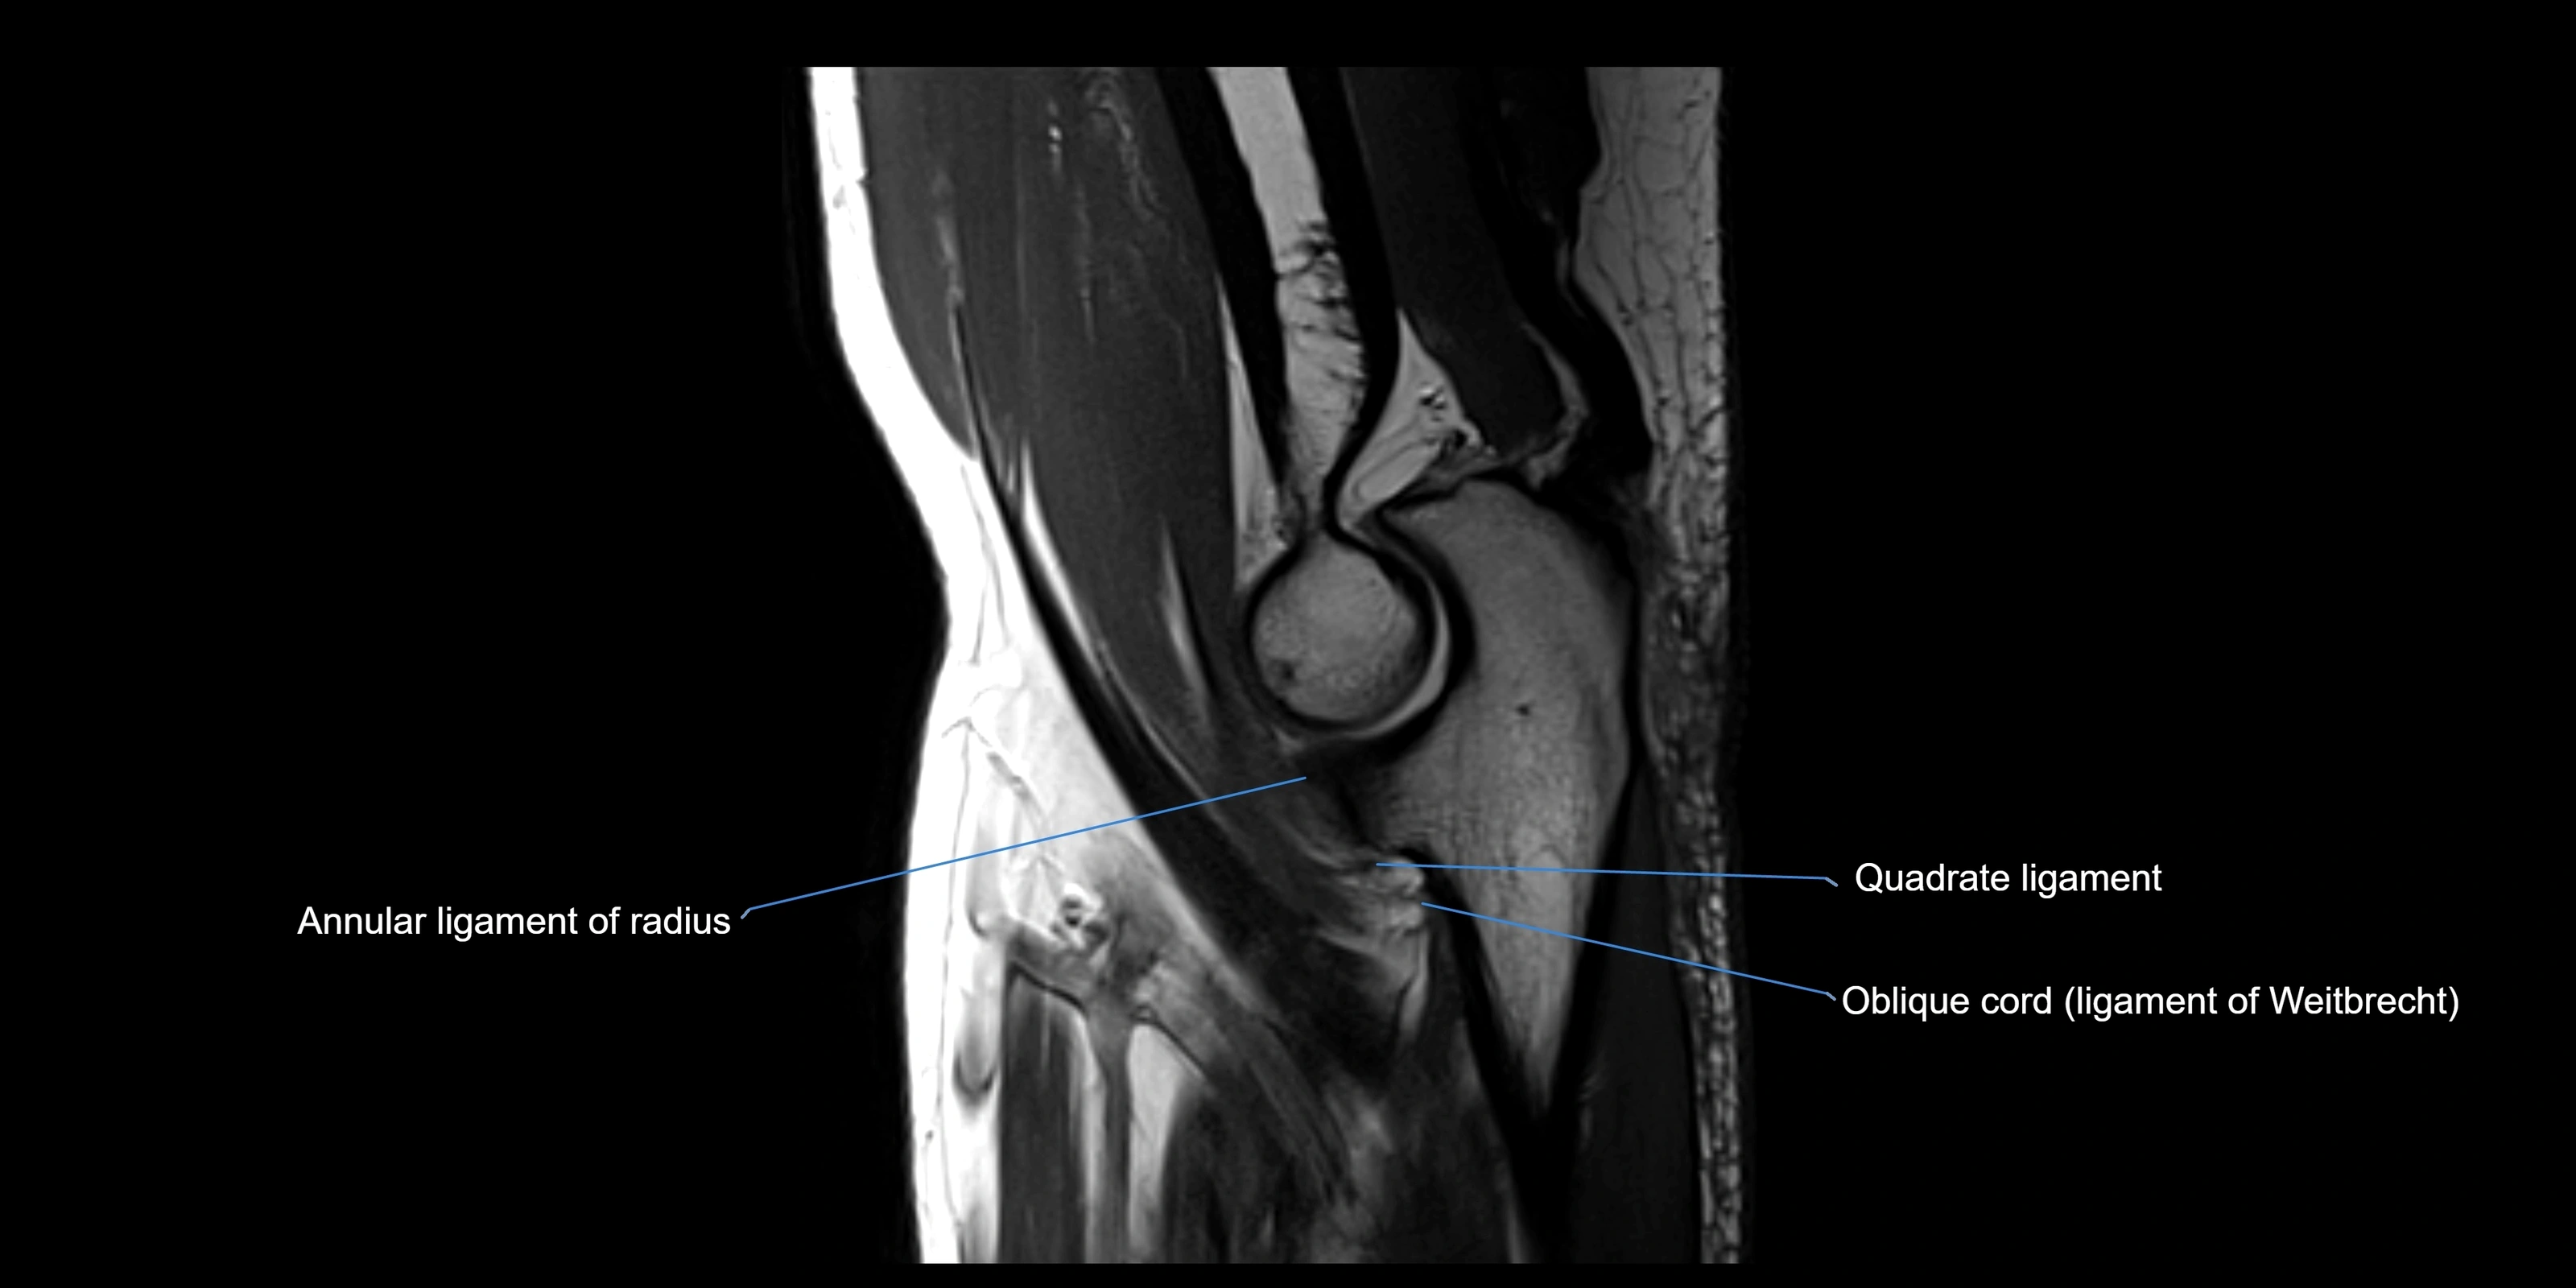

MRI Appearance

T1-weighted images:

• Ligament: low signal intensity (dark), appearing as a continuous band around the radial head.

• Adjacent fat and marrow: bright, creating contrast with the ligament.

• Thickening or disruption indicates injury or fibrosis.

• Joint capsule and synovium seen as thin low-signal lines contiguous with ligament margins.

T2-weighted images:

• Ligament: low signal (dark) with clear delineation from joint fluid.

• Fluid or edema: bright hyperintense, separating or surrounding the ligament in partial tears.

• Complete tear: discontinuity or non-visualization of ligament fibers, often with joint effusion.

MRI images

image